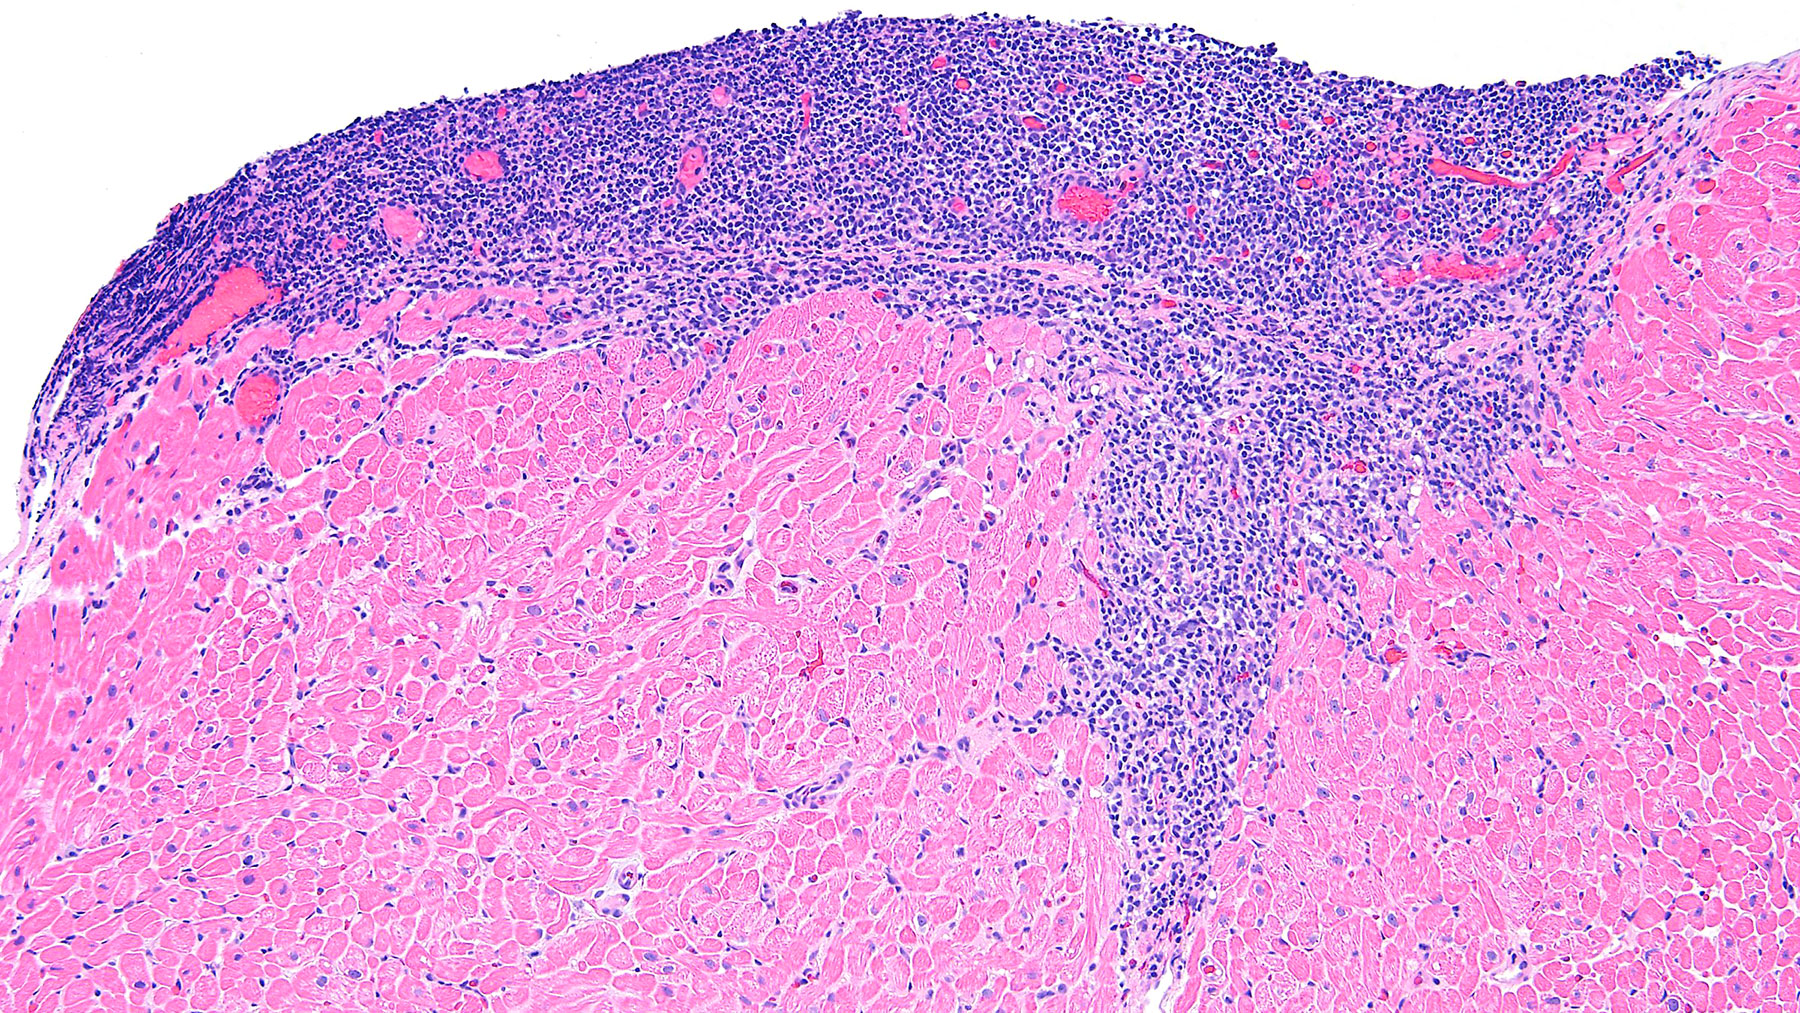

Figure C. CD21 (10x)

Histology: Figure A shows endocardium with a large focus of mononuclear inflammatory infiltrate spreading deeper between the myocardial fibers: this infiltrate shows focal myocyte encroachment and includes some plasma cells and a central capillary vessel. CD4, CD8 and CD20 are all positive (Figure E, F and B). CD21 is also positive which is a strong indicator of quilty effect. (Figures C and D). Trichrome staining shows no significant fibrosis (Figure G)